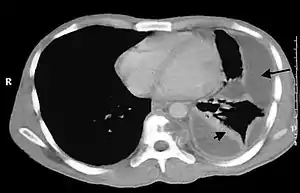

Empiema pleural (também conhecido como piotórax ou pleurite purulenta) corresponde ao acúmulo de pus na cavidade pleural. A maioria dos empiemas pleurais surgem a partir de uma infecção no pulmão (pneumonia), frequentemente associada com derrames parapneumônicos.[1]

A contaminação da cavidade pleural desencadeia um processo inflamatório com várias fases distintas. Inicialmente observa-se uma fase exsudativa, caracterizado por líquido fluido, livre e não septado na cavidade pleural. Esse derrame pode ser inicialmente estéril. Na fase fibrino-purulenta, o exsudato é substituído por uma secreção purulenta espessa, rica em polimorfonucleares e fibrina que se organiza produzindo septações. Finalmente, com a proliferação dos fibroblastos, surge uma membrana envoltória mais espessa e consistente, que restringe a expansão do pulmão. O líquido torna-se denso e cremoso, limitado entre as septações que constituem a parede do empiema.